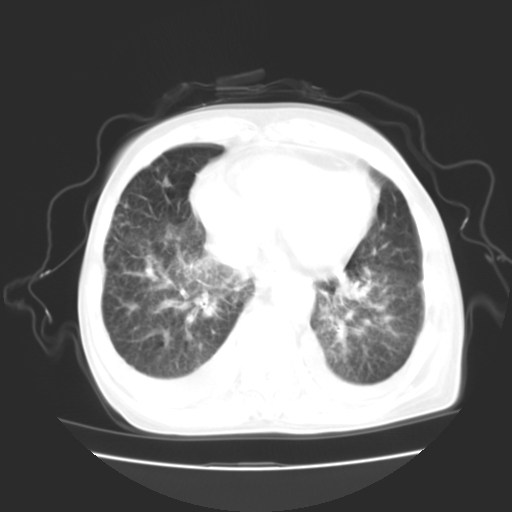

女70y乳腺ca(针吸活检)

多部位转移瘤的诊断可以肯定,我的疑问是:双肺对称高密度影及胸水是否为心衰肺水肿,病人体虚弱,不好意思图象传的乱![em9]

肺部病变为淋巴转移,肝脏转移,及局部淋巴转移。胸水可能为淋巴回流受阻(血性的考虑胸膜转移)

癌性淋巴管炎,肝脏转移,瓷胆囊

1)左侧乳腺癌并左侧腋窝及纵隔淋巴结转移,两肺淋巴道转移(癌性淋巴管炎),肝脏多发性转移。2)双侧胸腔积液。3)慢性胆囊炎。

3、双肺癌性淋巴管炎;

1)左侧乳腺癌并左侧腋窝及纵隔淋巴结转移,肝脏多发性转移。2)双侧胸腔积液伴双肺蝶翼样磨玻璃高密度影,双侧肺门血管影增粗(图像不全,肺门层面没纵隔窗),考虑心功能不全所致。3)慢性胆囊炎伴壁钙化。